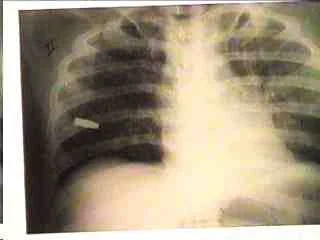

Loose contact shotgun wound and a larger, more ragged exit wound.

- Entrance

- Exit